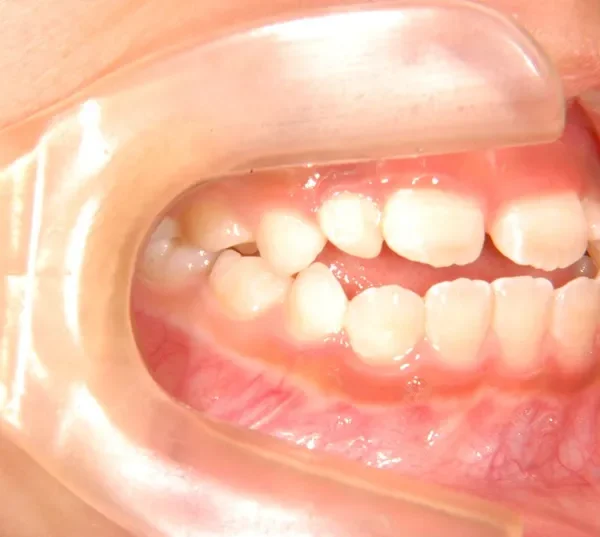

【子供の矯正(一期)】叢生・開咬・前歯で噛めない・舌癖・7歳女児【M.O様】

治療終了後

治療回数31回、4年11ヶ月の治療期間で矯正治療を終了しました。

主訴が改善され、ご満足頂きました。